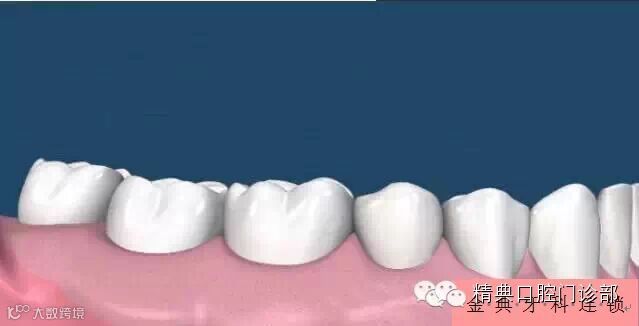

图片一、您以前有一口健康漂亮的好牙。